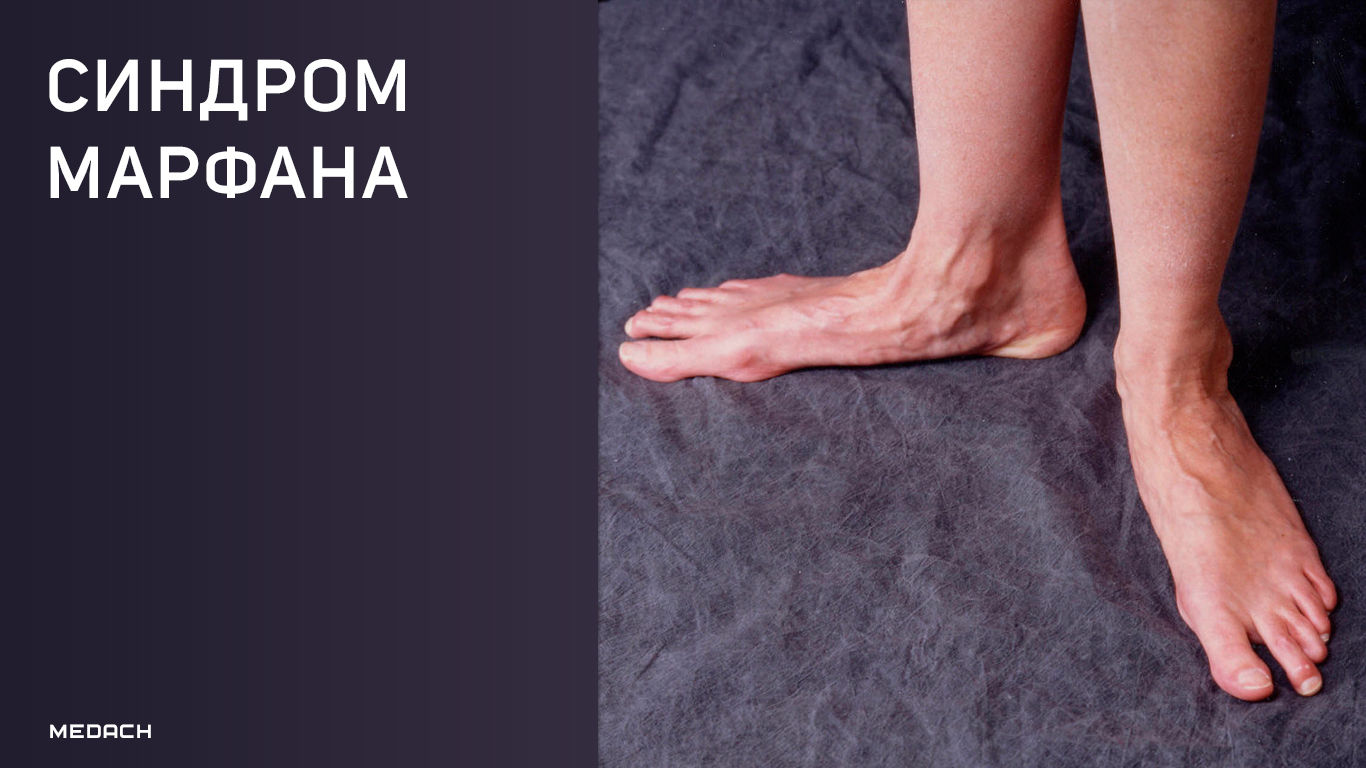

Sindrom marfana tema nauchnoj stati po klinicheskoj medicine chitajte besplatno tekst nauchno issledovatelskoj raboty v elektronnoj biblioteke kiberleninka (Тип файлу jpg)

Sindrom Marfana Tema Nauchnoj Stati Po Klinicheskoj Medicine Chitajte Besplatno Tekst Nauchno Issledovatelskoj Raboty V Elektronnoj Biblioteke Kiberleninka

Sindrom marfana tema nauchnoj stati po klinicheskoj medicine chitajte besplatno tekst nauchno issledovatelskoj raboty v elektronnoj biblioteke kiberleninka (Тип файлу jpg)

Sindrom Marfana Tema Nauchnoj Stati Po Klinicheskoj Medicine Chitajte Besplatno Tekst Nauchno Issledovatelskoj Raboty V Elektronnoj Biblioteke Kiberleninka